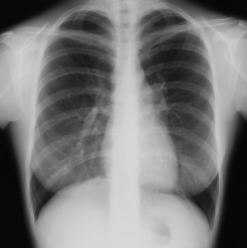

◆胸部レントゲン撮影

帝王切開などの手術を予定している場合に胸のレントゲン写真を撮ります。

肺や心臓の状態を確認するためです。